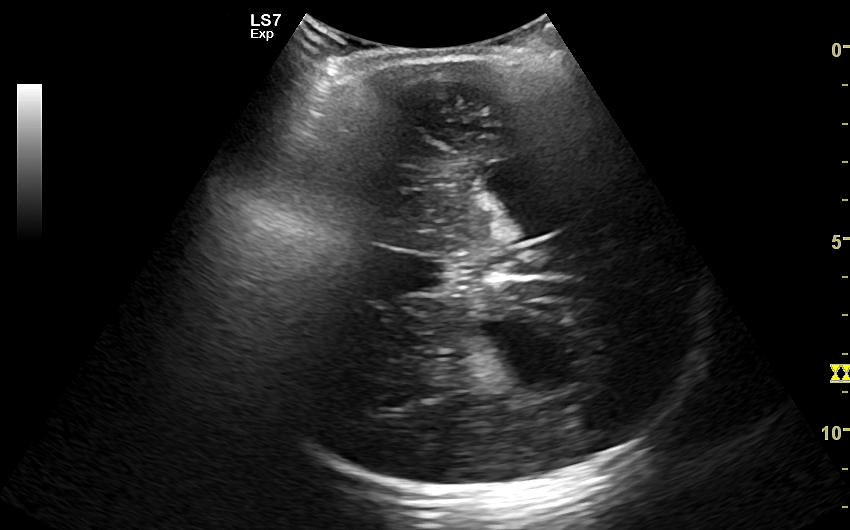

USG główki to podstawowa metoda diagnostyczna mózgu i struktur okołomózgowych u wcześniaków, noworodków i niemowląt. Badanie jest bezbolesne i nieryzykowne w porównaniu do rezonansu magnetycznego, podczas którego dziecko poddawane jest znieczuleniu ogólnemu. Przeprowadzenie szerokiego i szczegółowego badania USG główki jest możliwe aż do momentu zarośnięcia ciemiączka, czyli chrzęstnej struktury w pokrywie czaszki. Ze względu na cienką kość skroniową czaszki dziecka w późniejszym okresie możliwa jest wciąż częściowa ocena mózgowia w badaniu USG. Ambulatoryjne badanie USG przezciemiączkowe zwykle zalecane jest przez neonatologa, pediatrę lub neurologa dziecięcego w celu oceny mózgu wcześniaków, dzieci z małą masą urodzeniową, dzieci po epizodzie niedotlenienia lub krwawienia wewnątrzczaszkowego w trakcie porodu lub okresu noworodkowego, a także w przypadku wystąpienia drgawek, podejrzenia wady układu nerwowego, np. wodogłowia.

W USG główki dziecka oceniane są struktury wewnątrzczaszkowe, tj. mózg wraz z jego układem komór wewnętrznych, sploty naczyniówkowe, istota biała mózgu i obszary jąder podstawy mózgu, morfologia zakrętów i bruzd mózgowia, przestrzeń przymózgowa, a w trybach dopplerowskich wybrane naczynia tętnicze i żylne mózgu, w tym zatoki żylne. Oceniane są również cechy ciśnienia śródczaszkowego. W opisie badania podawane są również wymagane przez neurologa tzw. wskaźniki komorowe oraz wymiary wybranych struktur.

Badania USG mózgu dziecka wykonywane w warunkach szpitalnych i ambulatoryjnych różnią się od siebie charakterem stwierdzanych patologii. W szpitalu dominują ostre krwawienia wewnątrzczaszkowe oraz śródmózgowe. Z kolei najczęstszymi chorobami i stanami patologicznymi, które spotyka się w trakcie badania USG przezciemiączkowego przeprowadzanego w warunkach ambulatoryjnych są pozostałości po krwawieniach dokomorowych oraz śródmózgowych w postaci poszerzenia układu komorowego i torbieli; pozostałości po uszkodzeniach niedokrwiennych w postaci leukomalacji okołokomorowej i zaników mózgowych; poza tym zmiany pozapalne i wodogłowie wewnętrzne bądź zewnętrzne. Sporadycznie wykrywane są wady rozwojowe oraz guzy mózgu.